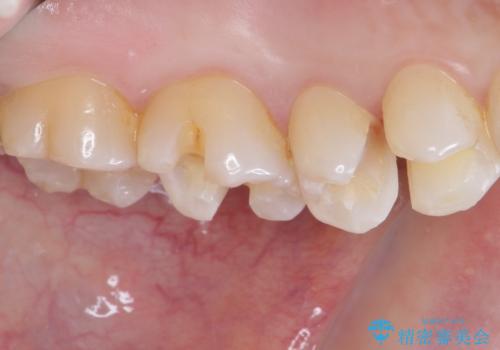

- 銀歯をセラミックにしたいとのことで来院された患者様です。

まず麻酔をして銀歯を外し、むし歯を除去し、形を整えて型取りします。

そして次の来院時、セラミックインレーを装着し、噛み合わせなどの調整を行います。

それを左右に分けて行いました。